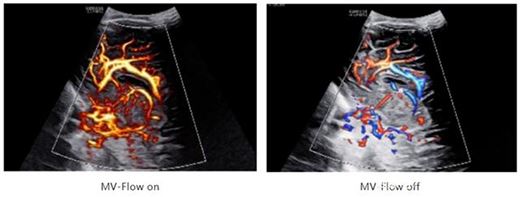

利器3:MV-Flow銳微成像、LumiFlow銳彩成像技術可非常靈敏顯示微小血管和超低速血流,清晰顯示胎兒顱內靜脈系統,配合對胎兒顱內竇匯(TH)的顯示可作為評估小腦幕位置改變的間接征象。

在臨床實踐與企業創新長久以來的深度合作下,這些之前非常困難的病例如今都可以被直觀的顯示,有效增加了診斷的精準度。